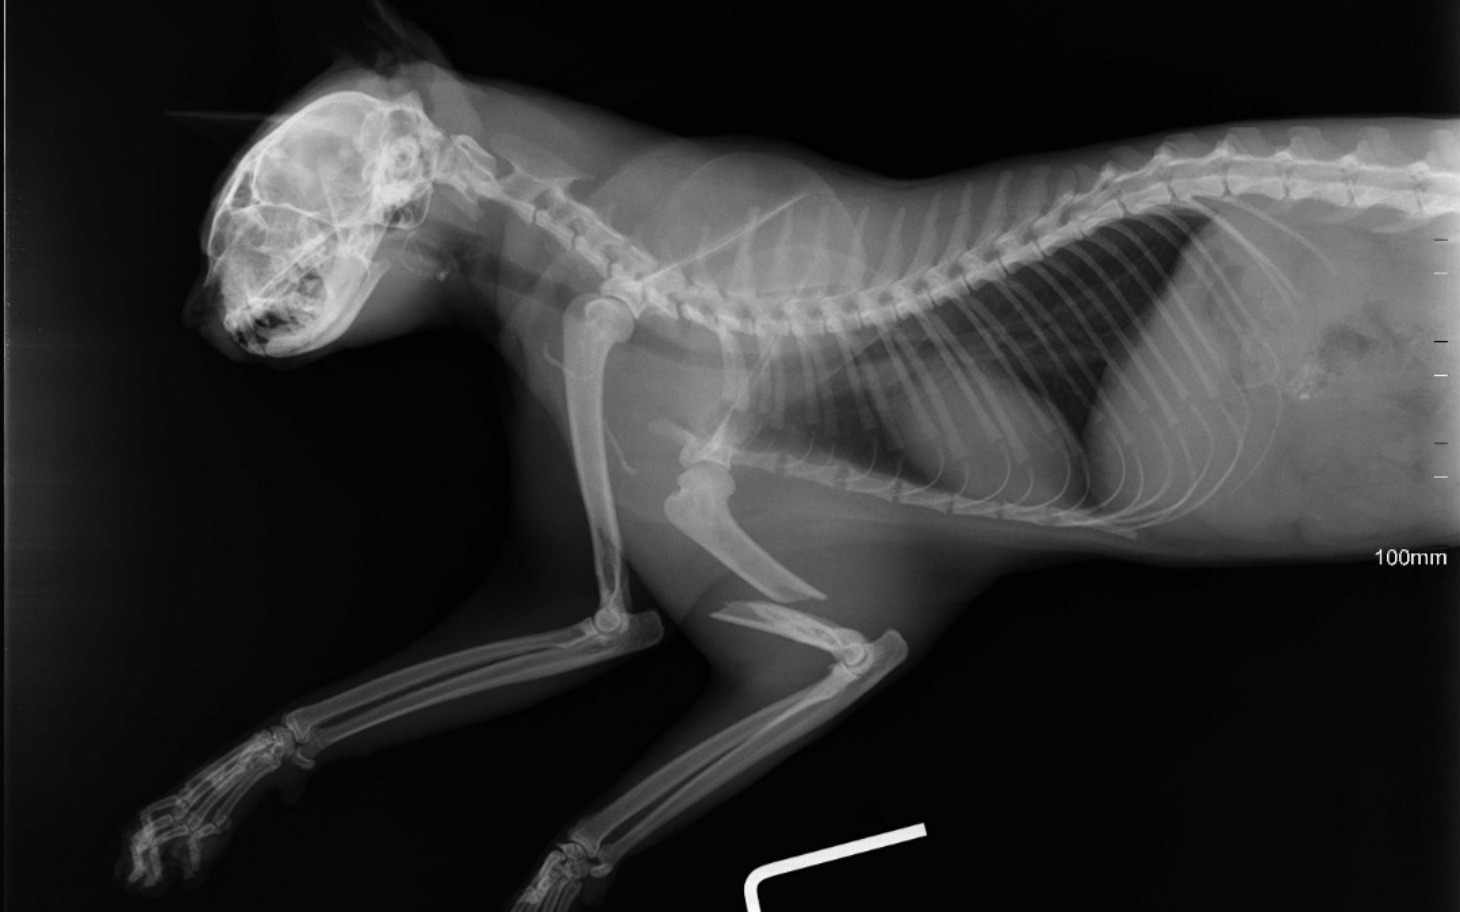

Po wstępnej diagnostyce wiemy już jedno – ma złamaną przednią łapkę. Każdy ruch to dla niego cierpienie. Każda próba postawienia kroku to ból, którego nie da się opisać.

Jutro ma zaplanowaną operację 15.04.2026. To jego jedyna szansa, żeby znów żyć bez bólu.